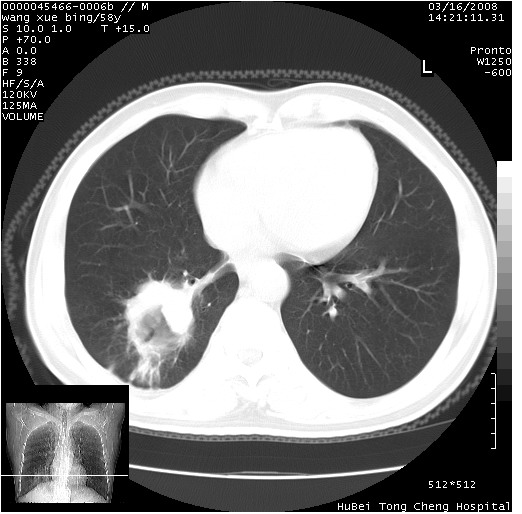

胸部ct轴位平扫(层厚10mm,螺距1.5,重建间隔10mm),图像如下:

右肺下叶团块及不规则空洞,内壁不规则,外缘见粗长毛刺,临近胸膜明显增厚并与病灶关系密切。支持考虑:右肺肺脓肿!建议穿刺病理检查待除外周围型肺癌!

右肺下叶见不规则厚壁空洞,内壁不规则,外缘见粗长毛刺,临近胸膜明显增厚并与病灶关系密切。支持考虑:周围型肺癌!

右肺下叶周围型肺癌伴空洞形成!征象比较明显!分叶、毛刺、胸膜凹陷征、厚壁空洞,壁结节!

空洞壁厚,不规则,其内可见壁结节,周围可见毛刺及阻塞性炎变,多考虑癌性病变.

空洞内壁不规整,有壁结节,周围有毛刺,支持癌性空洞。